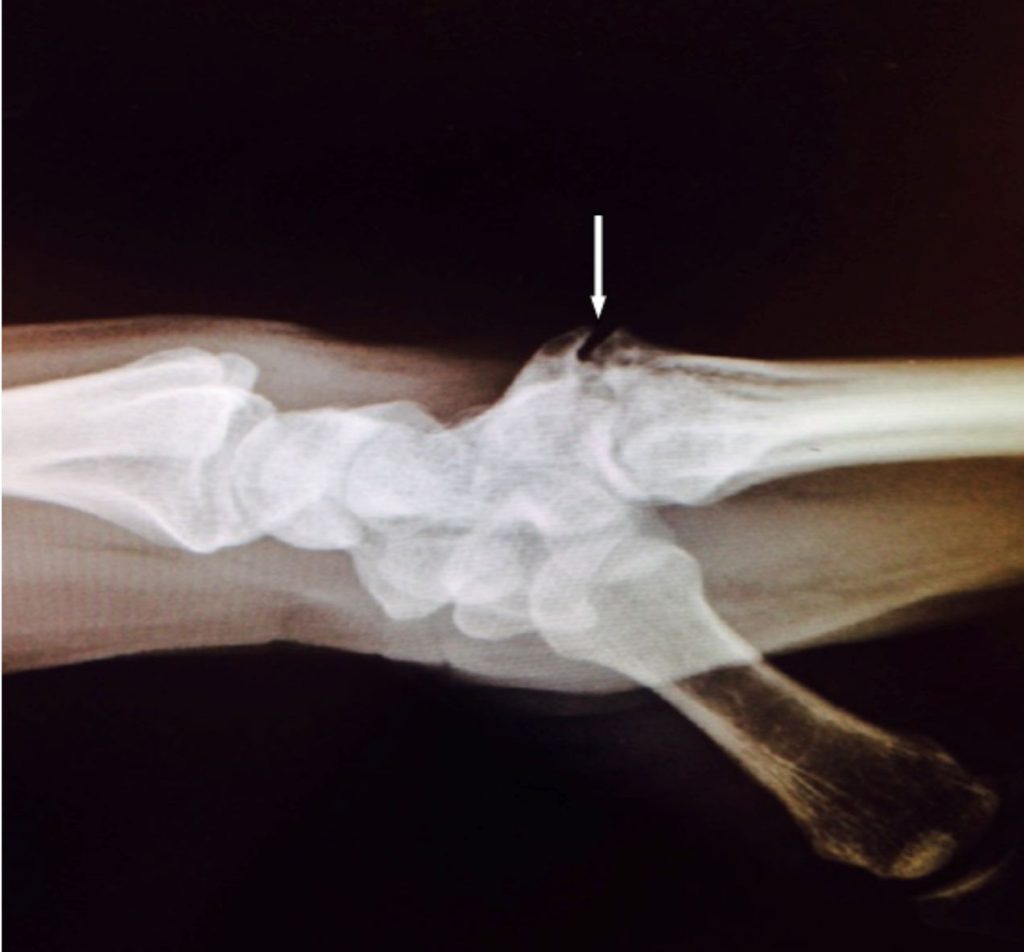

Los pacientes notan una protuberancia firme e inamovible en el dorso de la muñeca o la mano. Puede ser indoloro o molesto y doloroso. El dolor puede ocurrir con el movimiento hacia arriba y hacia abajo de la muñeca y/o al realizar la fuerza de agarre. También pueden llegar a producirse roturas (tanto dolorosas como indoloras) de los tendones extensores de los dedos sobre el carpal boss por el roce continuo. El carpal boss se confunde con frecuencia con un ganglión debido a su apariencia y ubicación similares (ver apartado de Gangliones). Algunos pacientes pueden tener un ganglión que se origina del propio carpal boss. En la Figura 1 se muestra una radiografía de un carpal boss.